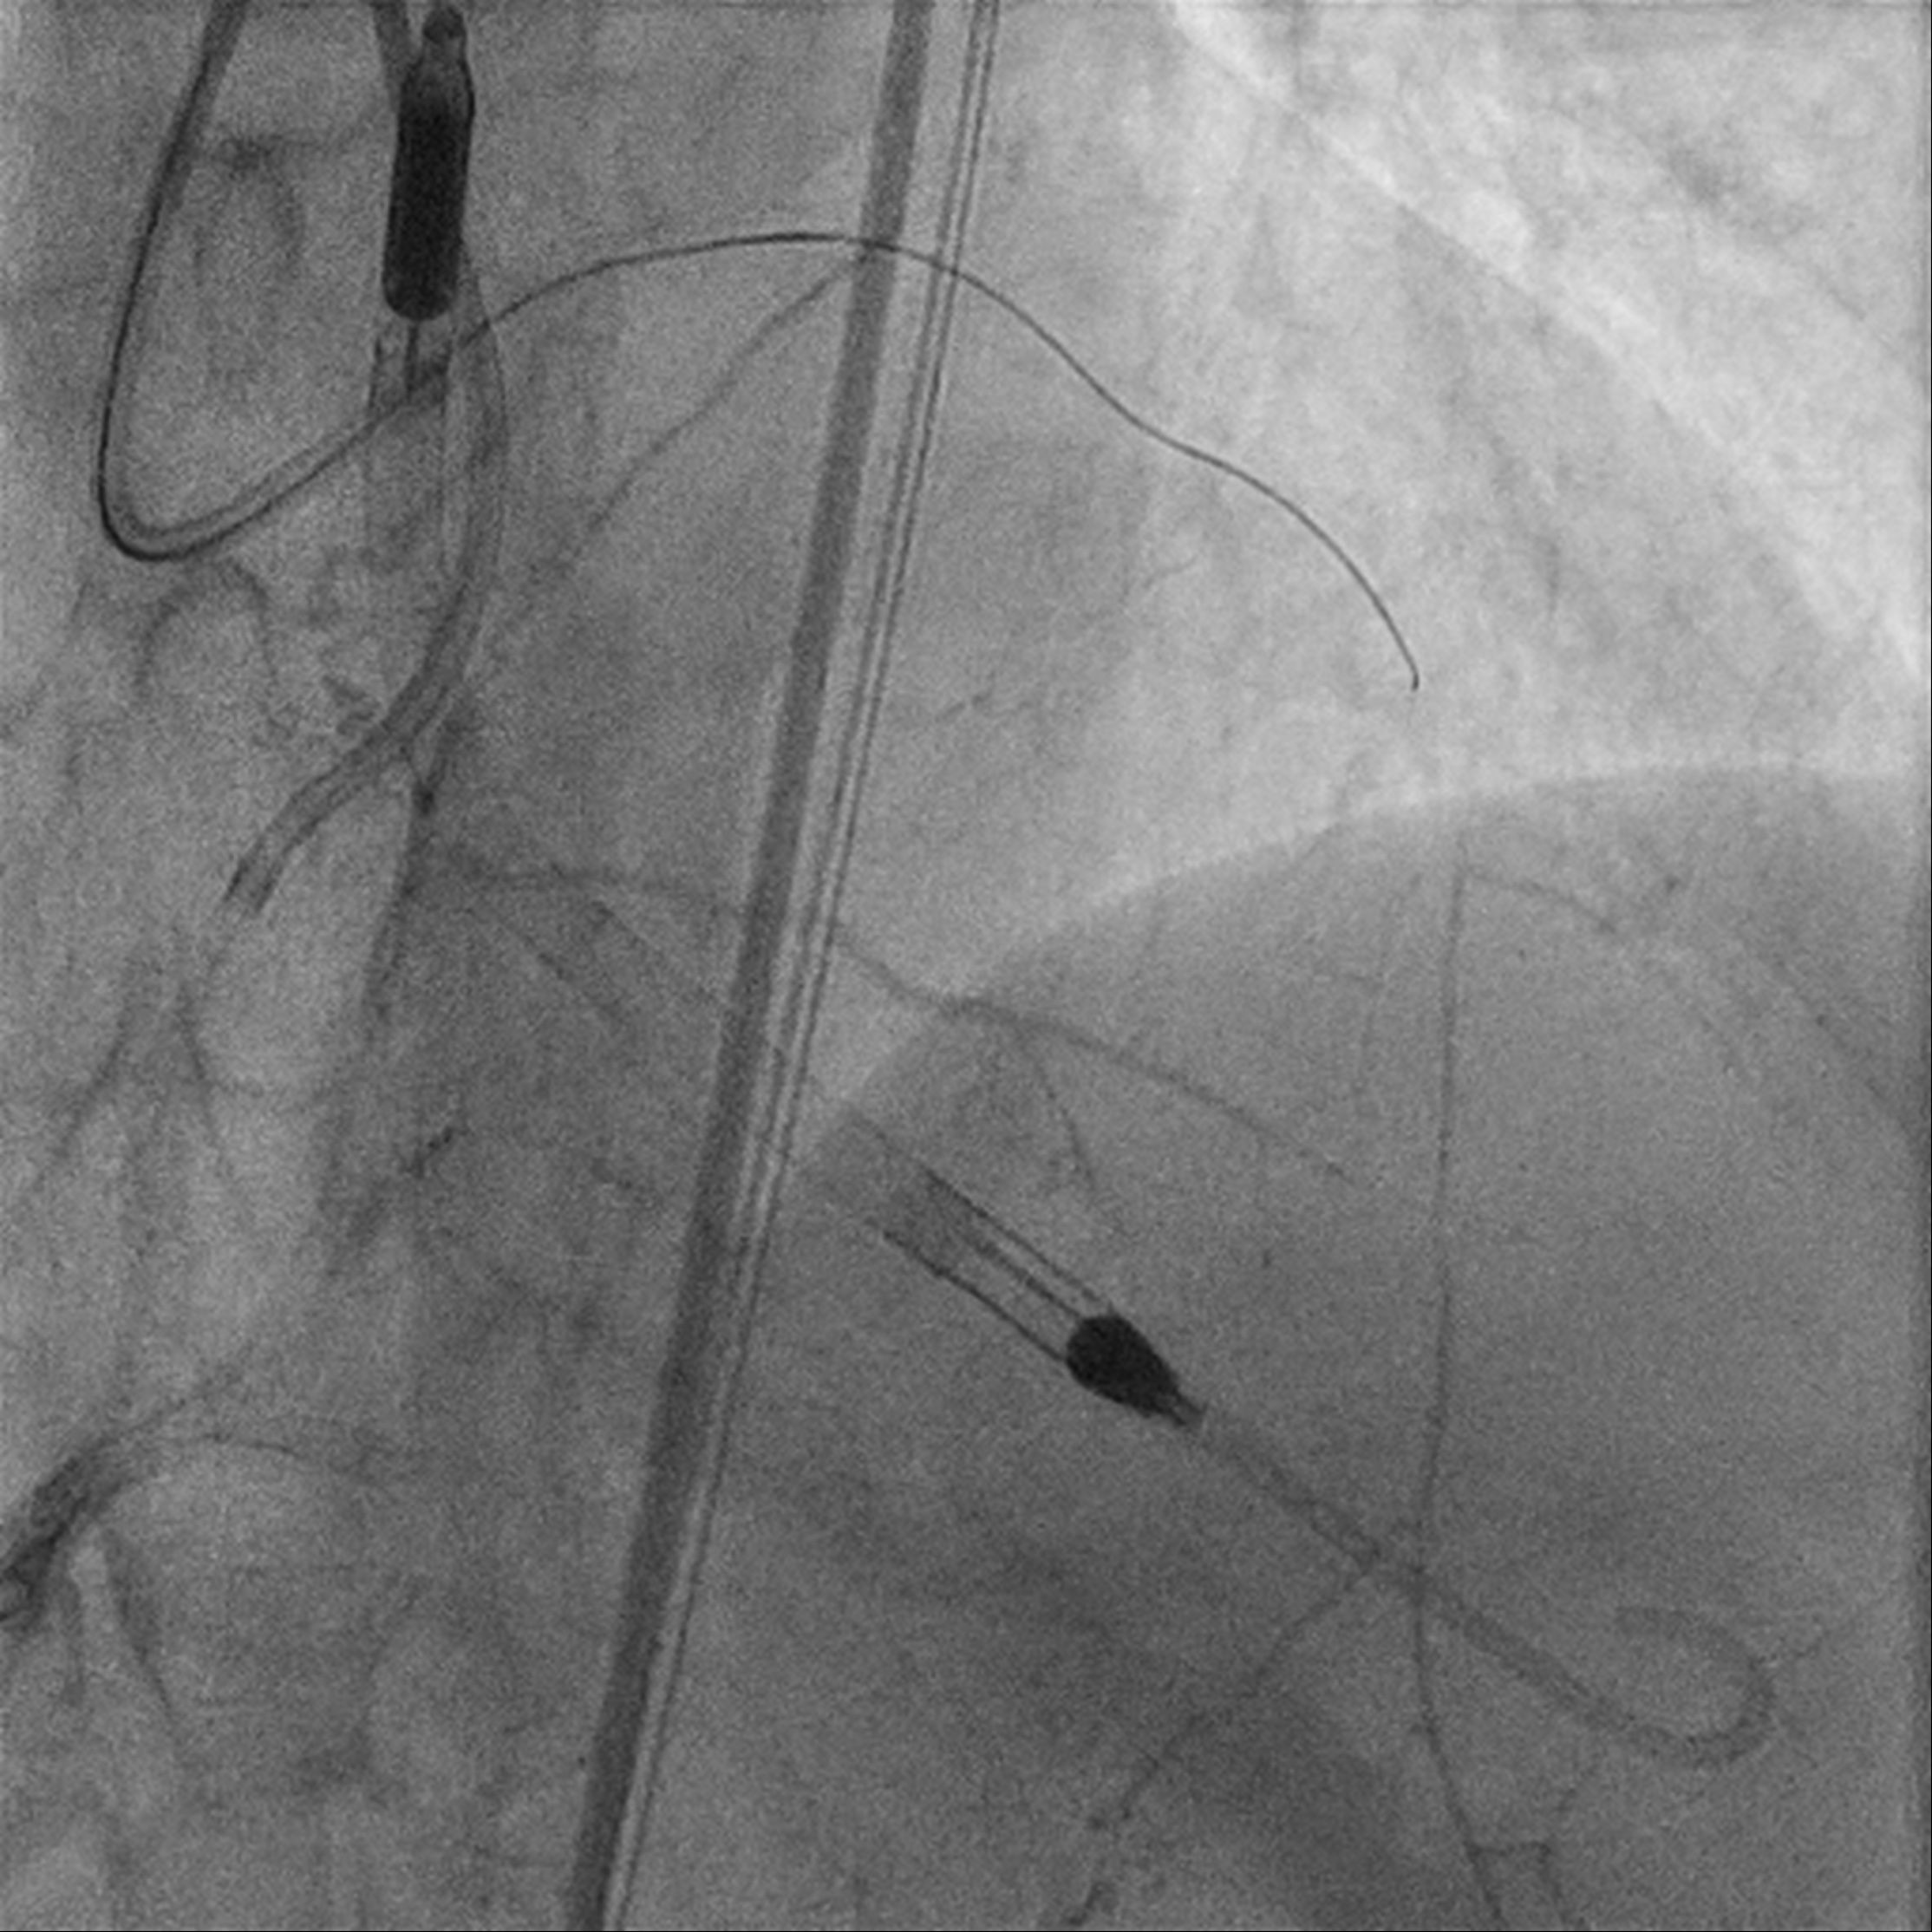

Procedural Step

Upfront MCS support using Impella CP via R CFA. Eccentric calcified plaque over m-dRCA, fibrofatty atheroma elsewhere. Initially plan for DCB over dRCA, however developed distal dissection, pRCA to PDA stented with total of 4 stents. Impinged PL branch ostium after stenting, branch rewired then POBA. Final IVUS and angiography shows good results. mLAD CTO crossed with Gaia 2 but Caravel unable to cross. CTO segment then dilated with semi compliant 0.85mm balloon then 1.5mm balloons. IVUS confirmed wire within true lumen throughout with long segments of calcific lesion. Rotational atherectomy with 1.5mm burr for 7 passes then further predilation with NC 2.75mm balloon. However, complicated with no reflow afterwards. Prolonged inflation of long segment compliant balloon followed by adenosine injection improved flow. IVUS showed calcium fracture but inadequate luminal gain, decided for IVL. Total of 8 cycles using 2.5mm shockwave, post IVUS showed improved luminal gain with more calcium cracking. DCB to m-dLAD afterwards for calcified diffuse disease. However developed no reflow after Paclitaxel-coated DCB which complicated with 1 episode of VT requiring cardioversion. Repeated adenosine injection improved flow, patient stabilized.